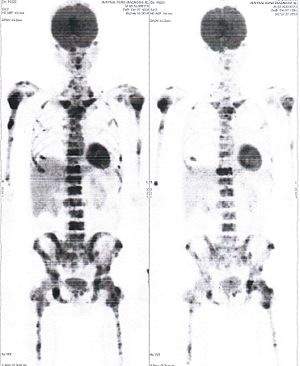

Below are some of the cases, from more than 80 cases we have treated so far with good results. When reading the PET/CT scans, the picture on the left is before treatment, and the picture on the right is after treatment. The intensity of black represents the activity of the cancer, but some black areas are not cancer: brain, heart, radioactive urine in bladder. For the heart, the intensity of black depends on the number of hours of fasting: if more than 10 hours, the heart is not even black, but if fasting is less than 6 hours, it is very black. The intensity of black in the brain can be variable in different scans depending on the brain activity at the time of the scan. The intensity of black in the radioactive urine can also be variable due to the hydration of patients and the time of injection of diuretic.

CASE NO: 5 (BREAST CANCER)

A middle-aged woman with breast cancer that has spread to the anterior chest wall, and numerous chemotherapy could not stop the spread of cancer. After a few treatment, almost all the cancer went into remission. About 6 months later, she is still in remission.

CASE NO: 6 (BREAST CANCER)

A middle-aged women treated for breast cancer now presents with massive liver metastases and a few bone metastases. She refused conventional chemotherapy and came to see us. After just 2 treatment, most of the cancer went into remission and those remaining are less active. Treatment will continue until complete remission.